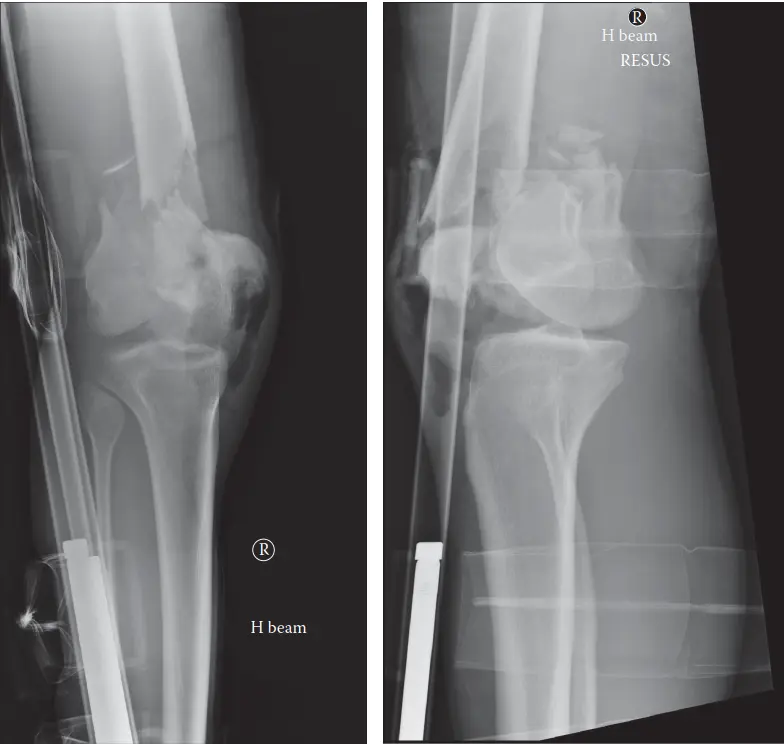

تُعد كسور عظم الفخذ السفلية (Distal Femoral Fractures) من الإصابات المعقدة التي تُصيب الجزء السفلي من عظم الفخذ، وتحديداً في منطقة تبعد حوالي 9 سنتيمترات عن خط مفصل الركبة. تُعرف هذه المنطقة باسم المنطقة فوق اللقمية أو داخل اللقمية، وهي حيوية لحركة الركبة واستقرارها. هذه الكسور ليست مجرد كسر بسيط في العظم؛ بل هي تحدٍ كبير لجراحي العظام والمرضى على حد سواء، نظراً لقربها من مفصل الركبة الحساس وأهمية هذا المفصل في الحركة اليومية.

إن أهمية هذه الكسور تكمن في قربها من مفصل الركبة، مما يجعل استعادة الشكل التشريحي الدقيق للمفصل أمراً حاسماً. أي عدم تطابق في سطح المفصل بعد الكسر قد يؤدي إلى مضاعفات طويلة الأمد مثل التهاب المفاصل ما بعد الصدمة (خشونة الركبة) وتيبس المفصل، مما يُعيق قدرة المريض على المشي وأداء الأنشطة اليومية.

يُستخدم نظام تصنيف AO/OTA بشكل أساسي لتصنيف كسور عظم الفخذ السفلية، وهو يُساعد الجراحين على فهم طبيعة الكسر وتحديد خطة العلاج المناسبة:

النوع C:

كسر كامل داخل المفصل (يُصيب كلتا اللقمتين والجزء القريب من المفصل).

يُشير هذا التصنيف إلى مدى تعقيد الكسر والحاجة إلى دقة أكبر في الاستعادة التشريحية كلما زاد التورط المفصلي.

يمر الشريان والوريد المأبضي عبر الحفرة المأبضية، خلف الجزء السفلي من عظم الفخذ مباشرةً. كما يقع العصب الظنبوبي والعصب الشظوي المشترك على مقربة شديدة. تُشكل كسور عظم الفخذ السفلية عالية الطاقة، خاصةً تلك التي تُصاحبها إزاحة كبيرة أو ميلان خلفي، خطراً كبيراً لإصابة الأوعية الدموية والأعصاب (مثل تمزق الشريان المأبضي أو العصب الشظوي المشترك). لذا، فإن التقييم العصبي الوعائي الشامل قبل وأثناء الجراحة إلزامي.

التشخيص الدقيق لكسور عظم الفخذ السفلية

وسائل التصوير التشخيصي

الأشعة السينية (X-rays):

- هي الفحص الأول والأساسي لتشخيص كسور عظم الفخذ السفلية.

- يتم أخذ صور من الأمام والخلف (AP) ومن الجانب (Lateral) للركبة وعظم الفخذ بالكامل (بما في ذلك مفصل الورك والكاحل) لتقييم المحور الميكانيكي للطرف.

- يمكن أن تُظهر الأشعة السينية وجود الكسر، نوعه (فوق اللقمة، داخل اللقمة)، مدى الإزاحة، ودرجة التفتت.

- قد تُستخدم أشعة الشد (Traction radiographs) لتقييم قابلية الكسر للرد.

التصوير المقطعي المحوسب (CT Scan):

- يُعد ضرورياً لجميع كسور المفصل (النوع B و C حسب تصنيف AO/OTA) والكسور خارج المفصل شديدة التفتت.

- يُوفر صوراً ثلاثية الأبعاد (3D reconstructions) تُظهر تفاصيل دقيقة عن حجم الشظايا، مدى الإزاحة، أي تدرج في السطح المفصلي، وأي انحشار عظمي.

- هذه المعلومات حاسمة للأستاذ الدكتور محمد هطيف لوضع خطة جراحية دقيقة، خاصةً لكسور المفصل التي تتطلب استعادة تشريحية مثالية.

خيارات العلاج لكسور عظم الفخذ السفلية

العلاج الجراحي (التدخل الجراحي)

يُعد التدخل الجراحي المعيار الذهبي لمعظم كسور عظم الفخذ السفلية المزاحة. الأهداف الرئيسية هي: